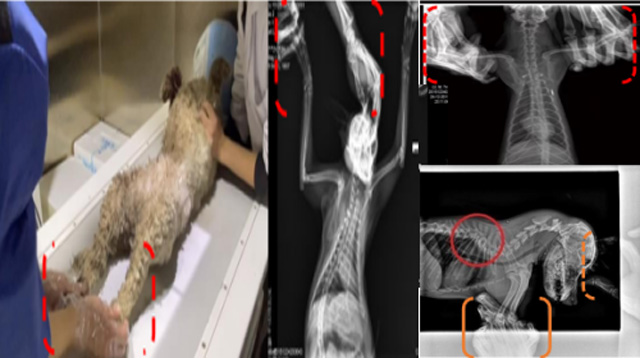

现在宠物医疗设备得到高速发展,现在有越来越多的宠物诊疗机构配置X射线装置如宠物DR。宠物骨折或者有其他疾病不能通过直观看出来的。宠物诊所医生都会使用宠物DR来做辅助检查。但是有时候宠物医生没有加强防护,就在宠物DR室给宠物拍X片做检查。这样也是会受到X射线的辐射。因为X射线上岗是属于职业病危害岗位。长期的辐射会对人体造成一定的危害。宠物医生也需要接受X射线照射的上岗前都必须进行放射工作人员的职业健康体检。体检不合格的话是不能担任放射工作的。未经上岗前职业健康体检的劳动者从事接触职业病危害作业的行为,已经违反了《中华人民共和国职业病防治法》第三十五条规定,依据《中华人民共和国职业病防治法》第七十五条规定,需要进行整改??睢?钩栉锓派湔锪苹疃?,在日常工作中,对本机构的X射线危害的职业病防治,需要知道并做到以下内容:

建造X射线机房时寻找专业防护施工队伍,对机房四方及上下方墙体进行屏蔽防护,尽可能隔室操作,使用铅防护门并安装工作指示灯张贴警示标识进行提醒。放射工作人员跟宠物主进入DR室需要穿戴铅衣、铅帽、铅手套等做好防护,减少X射线的辐射。避免暴露在照射范围中。宠物医生上岗前、在岗时、离开岗位时候的职业健康体检。如果检查异常就需要复查跟调离放射岗位。实施个人剂量监测和防护知识培训。并在劳动合同中向放射工作人员告知X射线危害相关内容。定期委托职业技术服务机构对机房防护、放射诊疗设备性能进行检测。不能忽略了对人的保护。